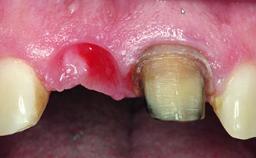

A 32-year-old female Caucasian patient with a compromised maxillary right central incisor was referred to us by a general dentist. Her chief complaints were discomfort and mobility of tooth 11 with unsatisfactory esthetics due to discoloration. The patient reported a previous trauma, some years earlier, as the origin of pathology on the afflicted tooth. Anamnesis was negative for any other dental or periodontal pathology in the remaining dentition. The patient did not take any medication and reported to be a light smoker (5–10 cigs/day). She had high esthetic expectations of her treatment. The extraoral examination revealed a high smile line with full exposure of her maxillary teeth and surrounding soft tissue in the area between the second premolars.

| Soft Tissue Grafting | Staged |

| Soft Tissue Contour and Volume | Slightly compromised |